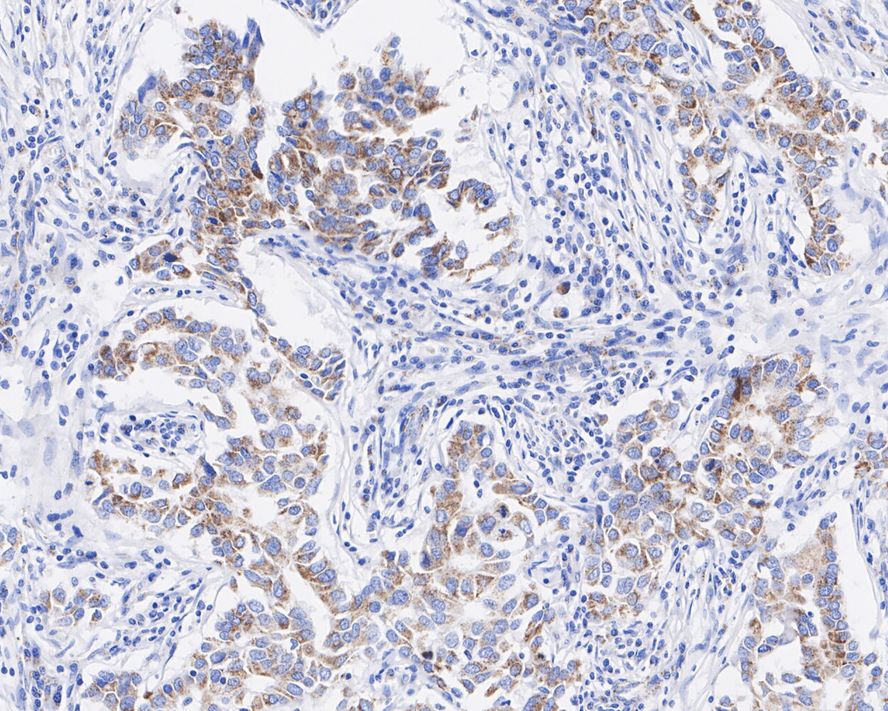

Catalog# HA721953

BMP4 Recombinant Rabbit Monoclonal Antibody [JE42-44]

IHC-P